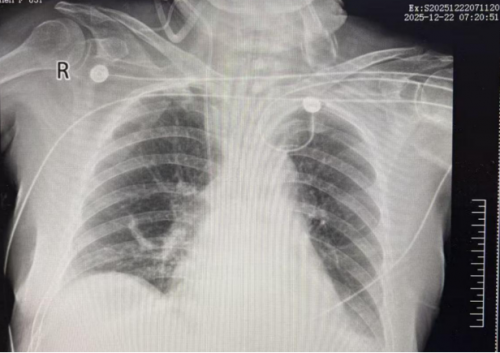

胸部 X线:支气管炎,右下肺炎症,左侧胸腔积液。

输血白蛋白加强利尿治疗。